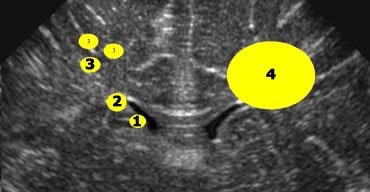

Measurement of the ventricular system needs to be performed on a symmetrical, easily reproducible view. The ventriculo-cranial ratio (VCR) is the ratio of distance between the lateral sides of the ventricles and the biparietal diameter. This is usually expressed as a percentage with a normal value of around 33-36% in a preterm infant. This value is of most use in monitoring the degree of change between successive measurements. An increasing VCR should trigger frequent reassessments with measurements of the cerebral resistive index (see below).